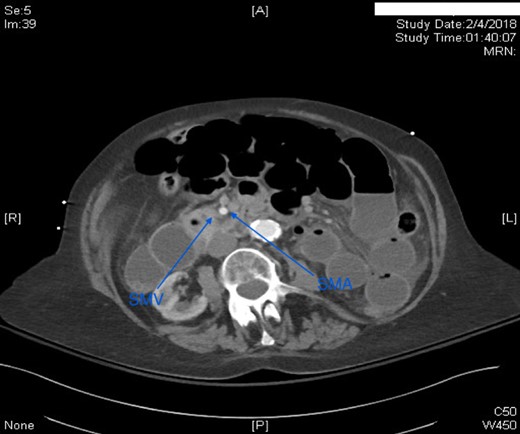

This case report presents an 80-year-old female with past medical history of Marfan syndrome with extensive cardiovascular manifestations including coarctation of the aorta, mechanical aortic valve and mitral valve replacement, heart failure with reduced ejection fraction (25–30%), and atrial fibrillation. The patient was admitted to the emergency general surgical service for complaints of acute onset colicky periumbilical abdominal pain, progressive abdominal distension, nausea and vomiting for 2 days. Emesis was described as non-bloody and non-bilious. Other pertinent history included one bowel movement 12 h prior to admission, which was non-bloody and inability to pass flatus for more than 24 h. No previous episode of abdominal pain of similar nature were elicitated. Physical examination was significant for mild abdominal distension and generalized tenderness to palpation in all quadrants without signs of peritonitis. Patient was afebrile and hemodynamically stable. Significant laboratory findings were INR of 2.20 (on warfarin for valve replacement), hyponatremia of 125, acute kidney injury with creatinine of 1.56. computed tomography (CT) of the abdomen/pelvis was significant for high-grade small bowel obstruction with a swirling of the superior mesenteric artery (SMA) and superior mesenteric vein (SMV) suggesting rotation of intestinal mesentery (Fig. 1) [5]. The SMV was located to the right of SMA, a reliable finding against intestinal malrotation [5] (Fig. 2). Further, there was no radiologic evidence of malrotation like transposition of SMA and SMV, the horizontal part of the duodenum not reaching medioventral line, and malposition of ileocecal junction [5]. The INR was not reversed with FFP and Vitamin K due to concern for stroke. Emergent exploratory laparotomy within 6 h of admission was performed which was significant for midgut volvulus with the small bowel rotating around the base of mesentery a complete 360°. There were no signs of ischemia, and hence manual untwisting of the bowel was performed [2, 5]. The cecum was noted to be on the right lower quadrant and ligament of Treitz was on the left upper quadrant. The small bowel mesentery was noted to appear long with narrow base and floppy likely contributing to hypermobility of the small bowel. The patients postoperative course was uneventful, and she was discharged to skilled nursing facility for further rehabilitation.

Axial CT scan of abdomen with IV contrast. SMV was located to the right of SMA.